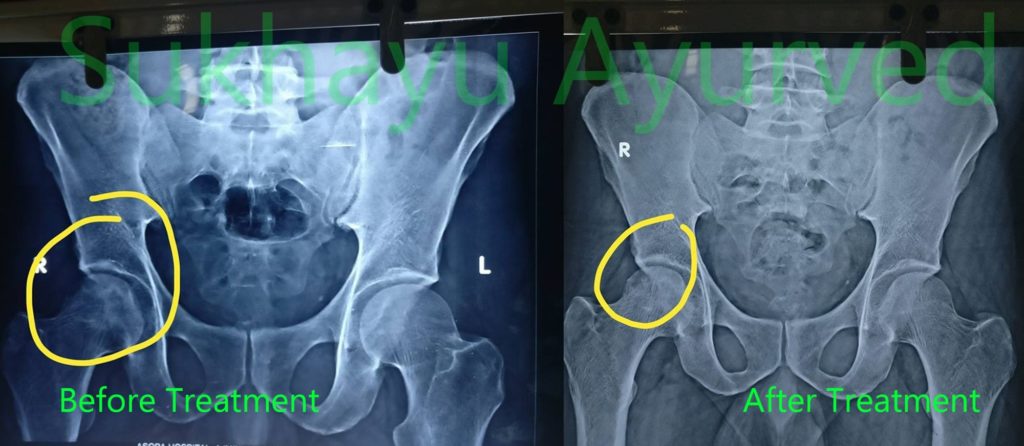

रोगी का नाम: श्री व्यास

उम्र : 45 साल

उपचार की कुल अवधि: 2 साल

गैर मादक एक पूरा जो नशे में मरीज। स्टेरॉयड के किसी भी इतिहास के बिना। वहाँ उनके मामले में दो कारकों थे।

श्री व्यास एक सामान्य जीवन जी रहा है। यही कारण है कि आयुर्वेद की वजह से है। Sukhayu सिर्फ इस तरह के मामलों के सफल इलाज के लिए एक माध्यम है।